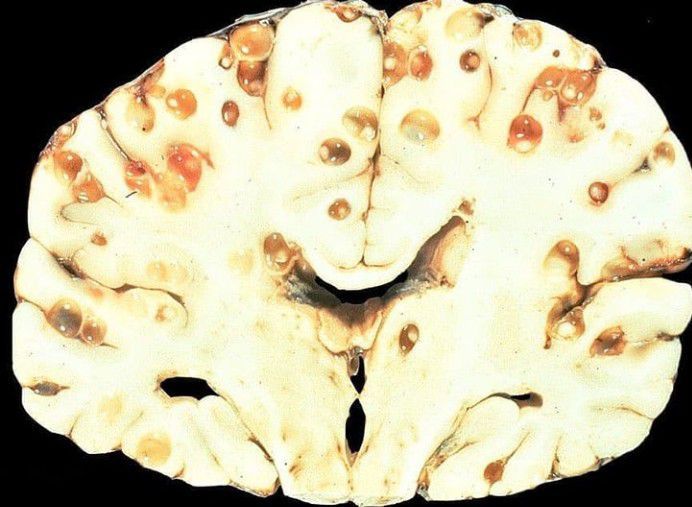

Neurocysticercosis is the result of accidental ingestion of eggs of Taenia solium (ie, pork tapeworm), usually due to contamination of food by people with taeniasis.The larval cysts can infect various parts of the body causing a condition known as cysticercosis. Clinical manifestations of neurocysticercosis vary with the locations of the lesions, the number of parasites, and the host's immune response . Many patients are asymptomatic. Possible symptomatic presentations include the following: Epilepsy: Most common presentation (70%) Headache, dizziness Stroke Neuropsychiatric dysfunction Credits: https://www.instagram.com/p/CSe7OAOMkD-/?utm_medium=copy_link